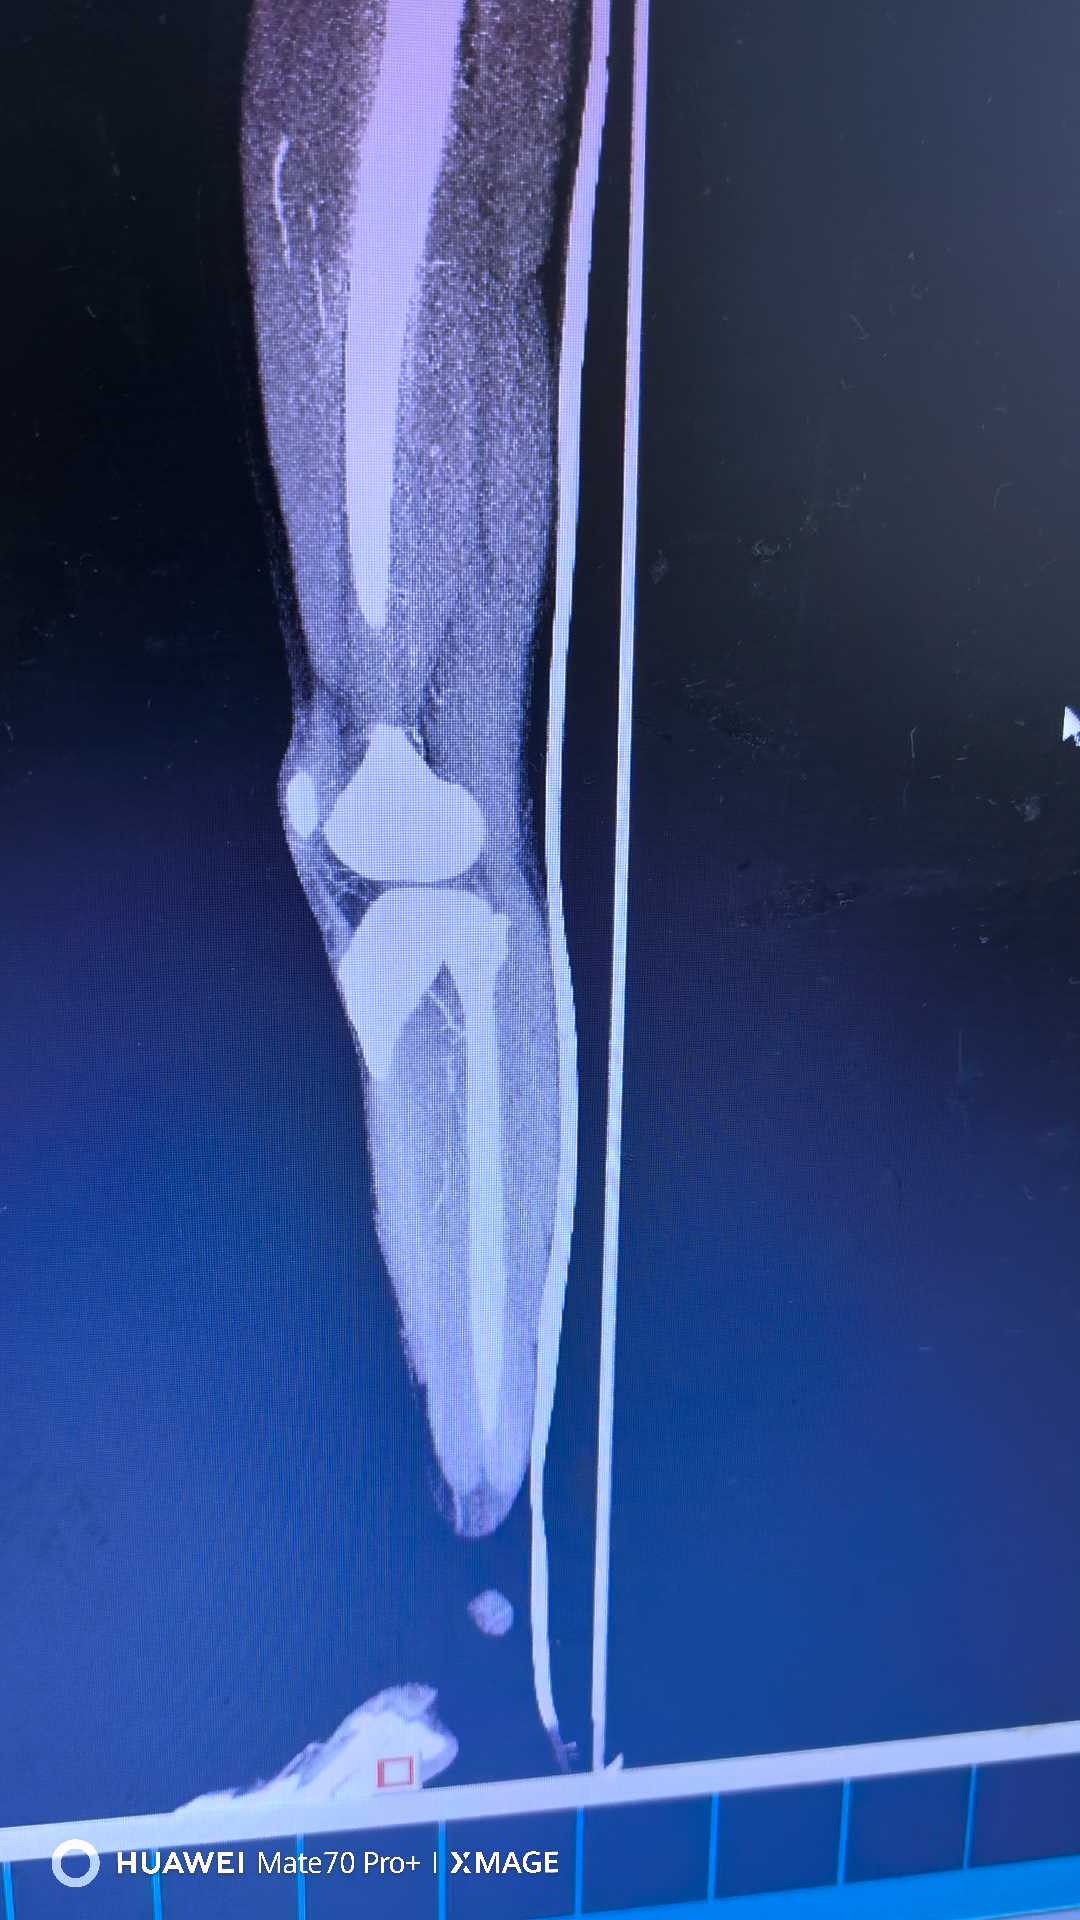

【检查】:

【临床诊断】:右下肢动脉闭塞(腘窝段)